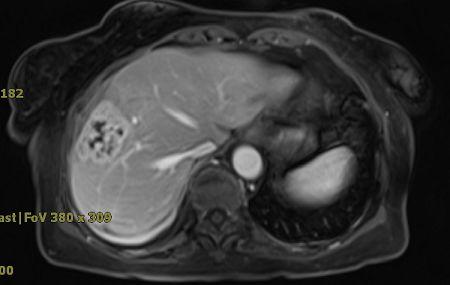

• 上中腹部MRI:肝右前叶VIII段肝脓肿穿刺术后改变,大小约3.8 cm×3.0 cm。范围内见结肠肝曲局限性增粗肿块影大小约3.2 cm×3.2 cm,周围界限清晰,周围未见增大淋巴结,占位病变可能(见图1)。

图1腹部MRI